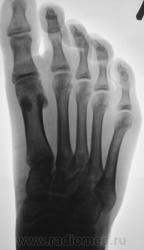

Пациент направлен на рентген-контроль после лечения.

С основной фалангой вопросов нет, посттраматический артроз гарантирован; есть ли похожий перелом средней фаланги? или мне показалось?

На мой взгляд, "кусочек" отвален.

Согласен...интересно - каков механизм, если Вам известны обстоятельства травмы?

Элементарно.

Господин "кирпич" из пьяных рук вывалился.

Понятно ... и вкось ребром на стопу то и упал...вопросов, как говориться, больше нет))))....